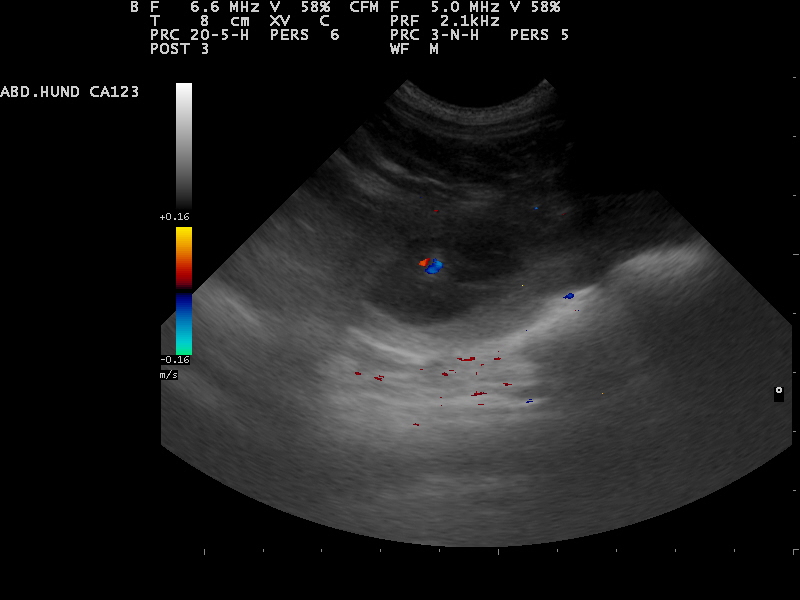

Hierfür eignet sich sehr gut die Gabe von Welpenfutter. Zu diesem Zeitpunkt kann mit einer Ultraschalluntersuchung

der Zustand der Trächtigkeit festgestellt werden. Besprechen Sie mögliche Risiken einer solchen Untersuchung mit dem Tierarzt.

Am 01.07.2014 waren wir zur Ultraschalluntersuchung und konnten

die ersten Bilder unserer Welpen bewundern.